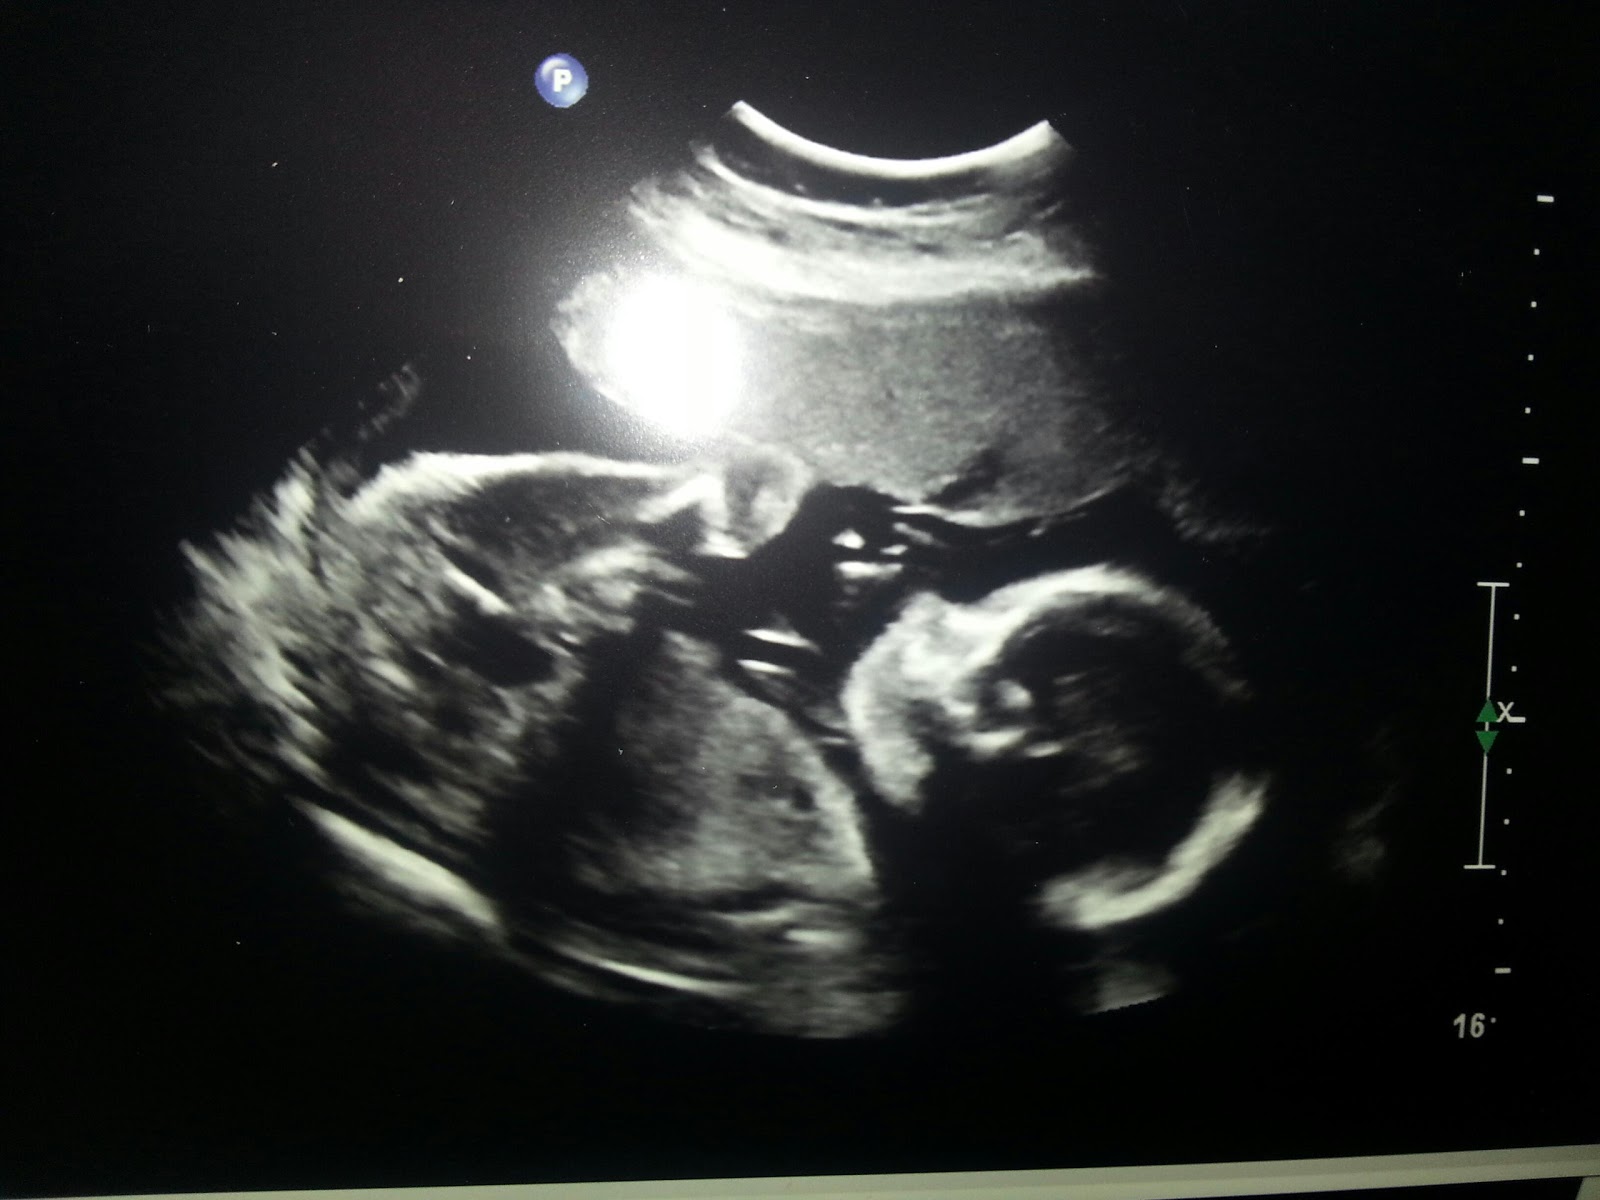

It's a Girl ! on July 30, 2013 Get link Facebook X Pinterest Email Other Apps Adrianna Marybelle Latuch ♡ Comments